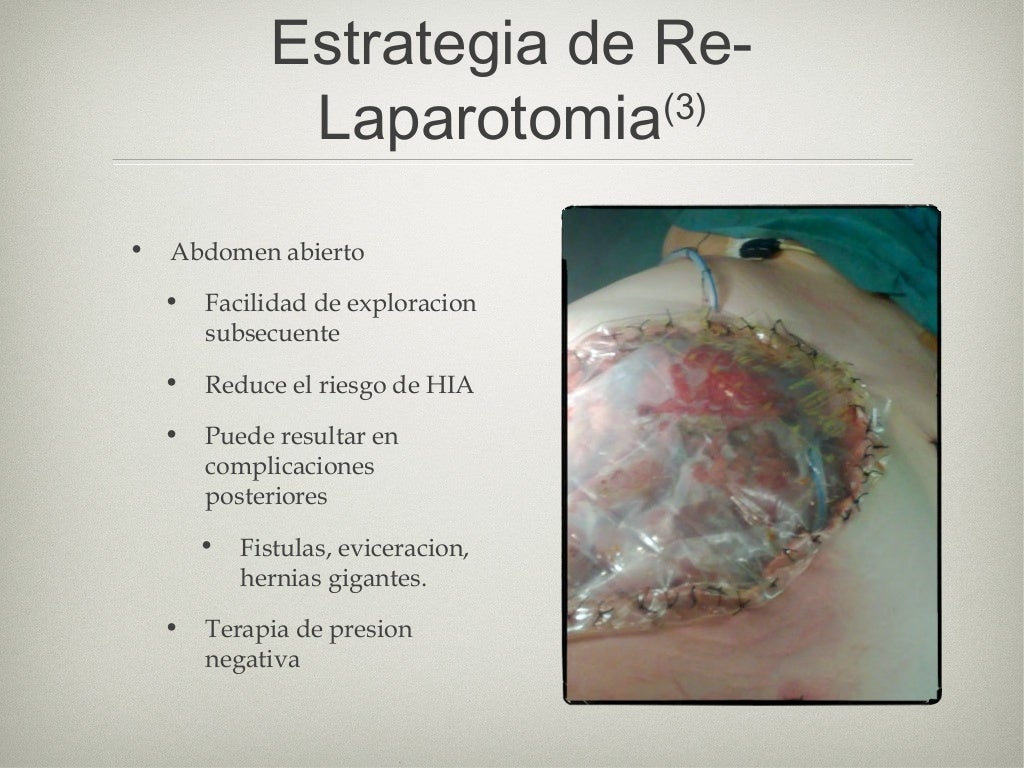

Sepsis intra abdominal